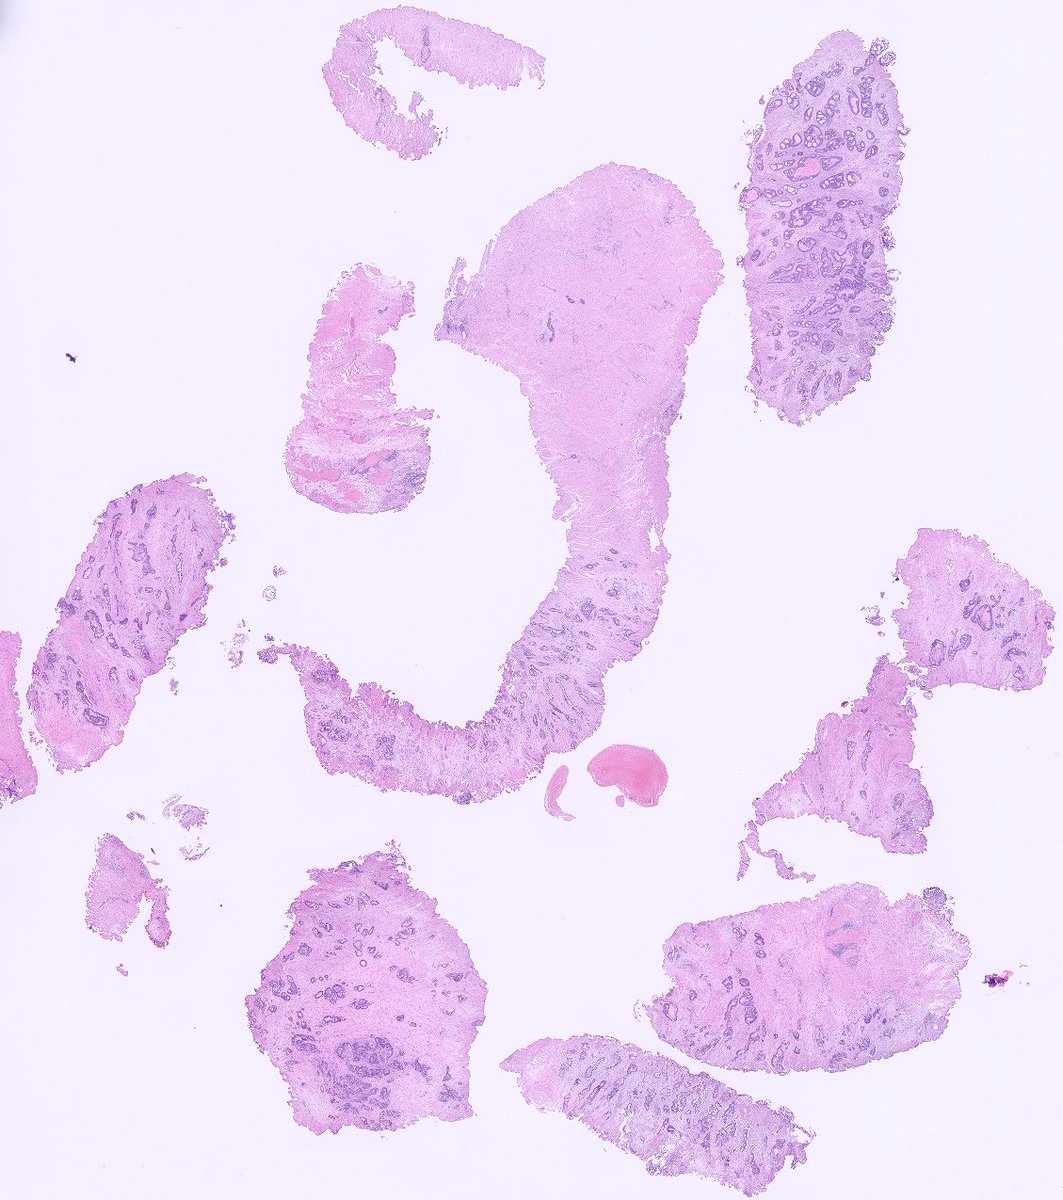

43 female, dilated CBD with stricture endoscopy: bulky bulging papilla with hyperplastic mucosal covering, which easily bleeds on touch, suggestive of an ampullary adenoma causing papillary distortion. Any thoughts on this ?#pathtwitter #GIpath

3

1